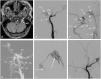

We report three cases of dural arteriovenous fistulae of the hypoglossal canal (HCDAVF) with different clinical and angiographic presentations and their treatment approach.